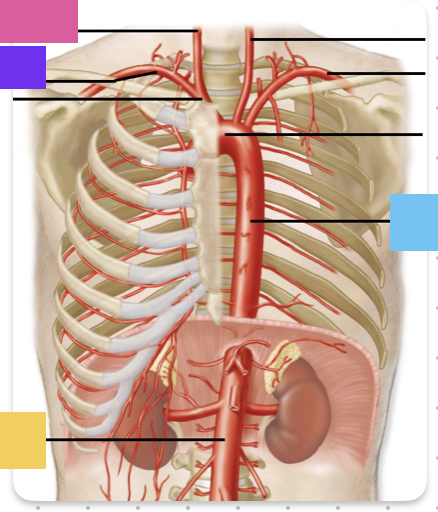

aortic arch

brachiocephalic trunk (blue)

right common carotid artery

right subclavian artery

left common carotid artery (grey)

left subclavian artery (black)

descending aorta

thoracic aorta

abdominal aorta